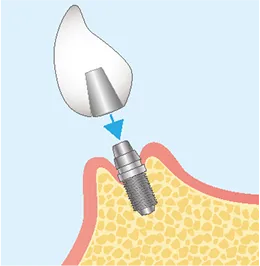

インプラント治療は、一般的に「一次手術」と「二次手術」の2段階で行われます。

流れを正しく理解することは、納得して治療を受けるために大切なステップです。

FLOW02

二次オペ

(アバットメントの装着)-

FLOW03

上部構造

(人工歯)の装着最終的な被せ物(上部構造)を製作・装着します。